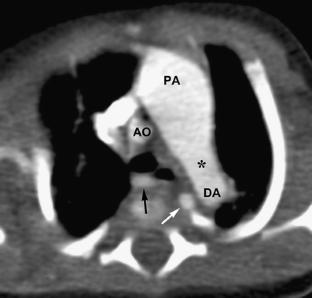

Fig. 3